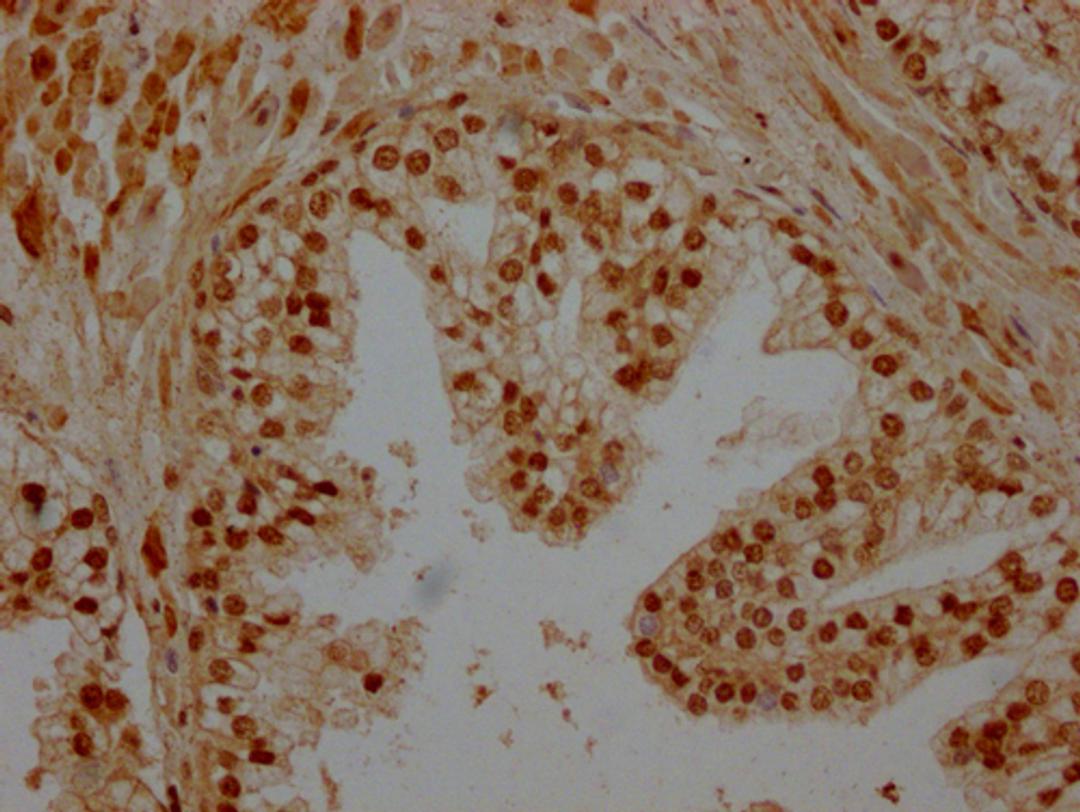

IHC image of CSB-PA851527LA11HU diluted at 1:200 and staining in paraffin-embedded human prostate cancer performed on a Leica BondTM system. After dewaxing and hydration, antigen retrieval was mediated by high pressure in a citrate buffer (pH 6.0). Section was blocked with 10% normal goat serum 30min at RT. Then primary antibody (1% BSA) was incubated at 4°C overnight. The primary is detected by a Goat anti-rabbit polymer IgG labeled by HRP and visualized using 0.05% DAB.